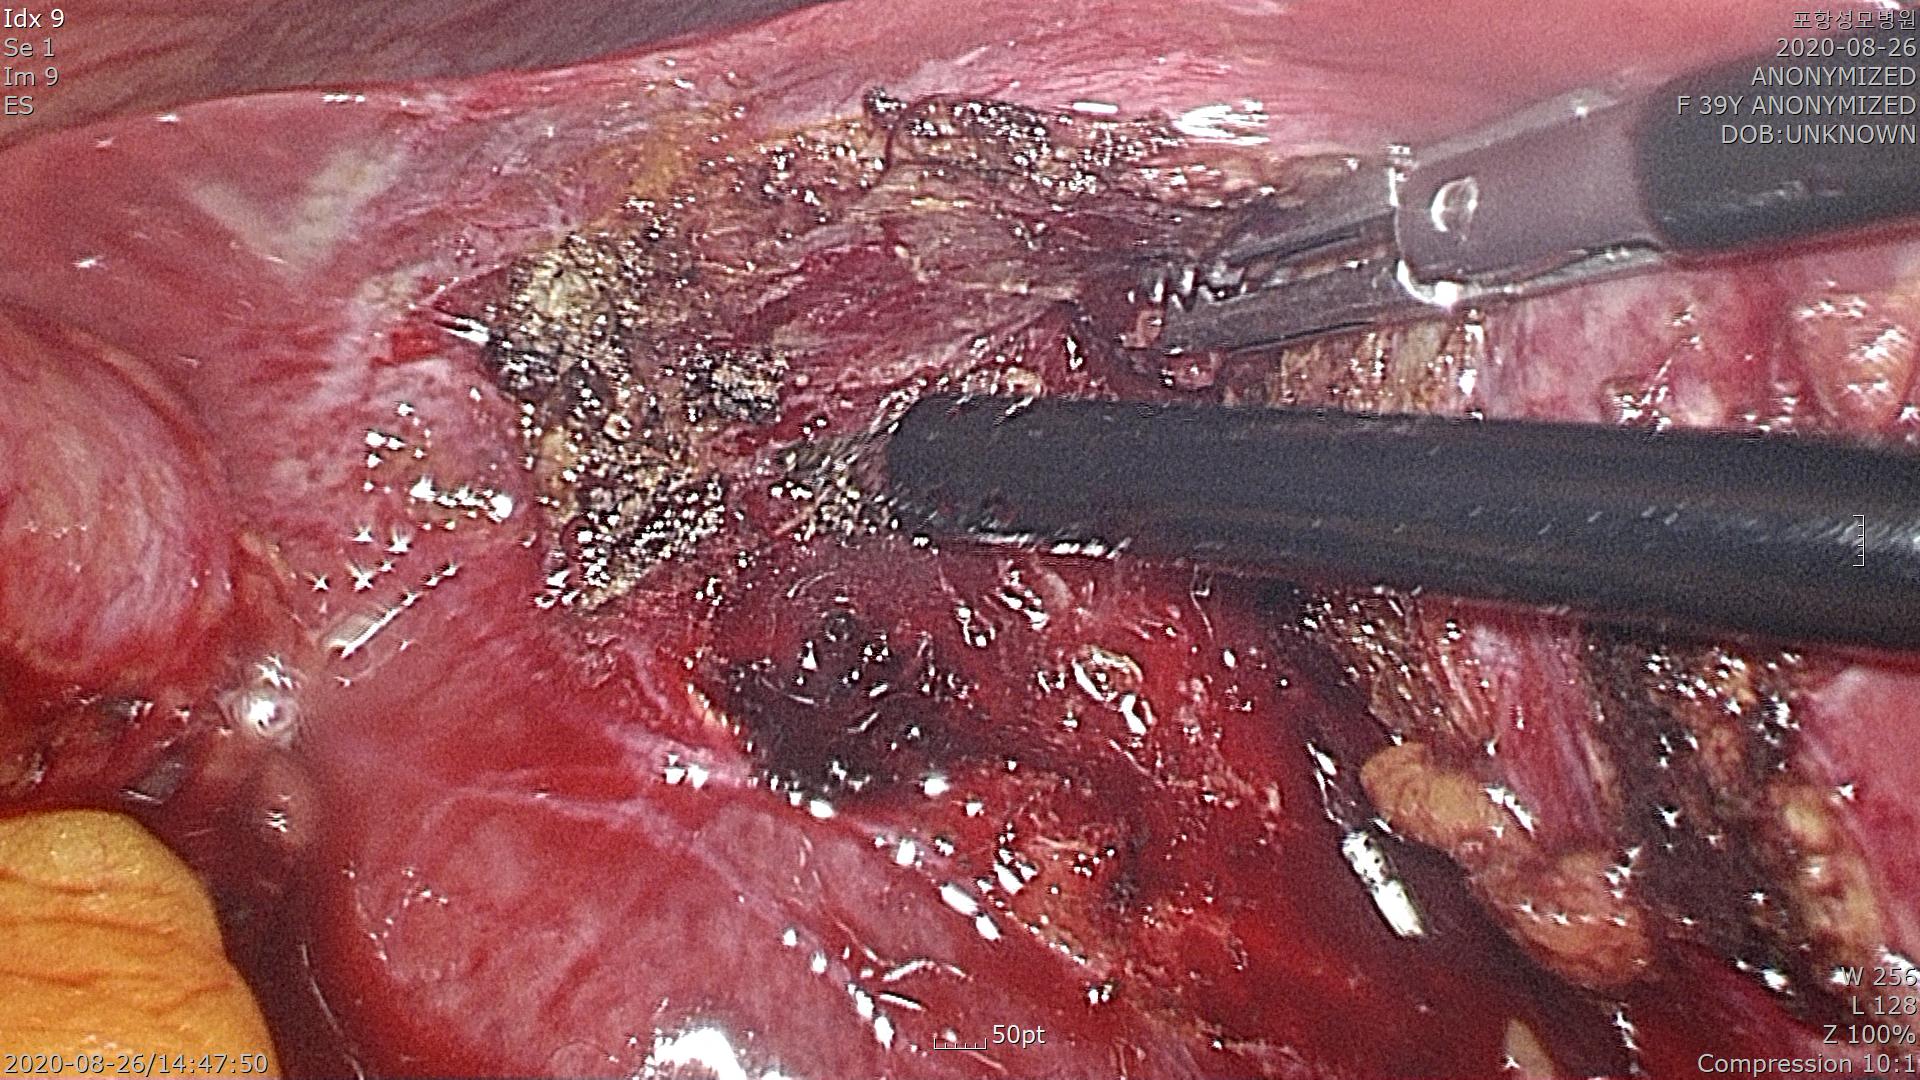

복강내에 카메라를 넣고 확인해 보니 염증이 심해 복강내에 있는 지방조직(대망, Greater omentum)이 담낭에 들러 붙어 있습니다.

조심스럽게 대망을 박리해서 담낭과 분리를 시킵니다. 담낭이 드러납니다. 일부 담낭벽에 괴사(Necrosis)가 있습니다. 담낭벽에 약간 회갈색으로 보이는 부분이 괴사가 진행되고 있는 부분입니다.

조금더 진행되는 경우에 담낭 천공(Perforation)이 일어나 복막염(Peritonitis)로 진행할 수도 있습니다.

담낭관(Cystic duct)를 확인하고 클립을 사용하여 결찰을 합니다. 담낭관 풀리지 말라고 3번이나 클립을 사용하여 결찰합니다.

간 후벽에 붙어있는 담낭을 모두 제거했습니다. 지혈을 하고 수술을 마칩니다.

수술은 특별한 합병증없이 잘 끝났습니다.